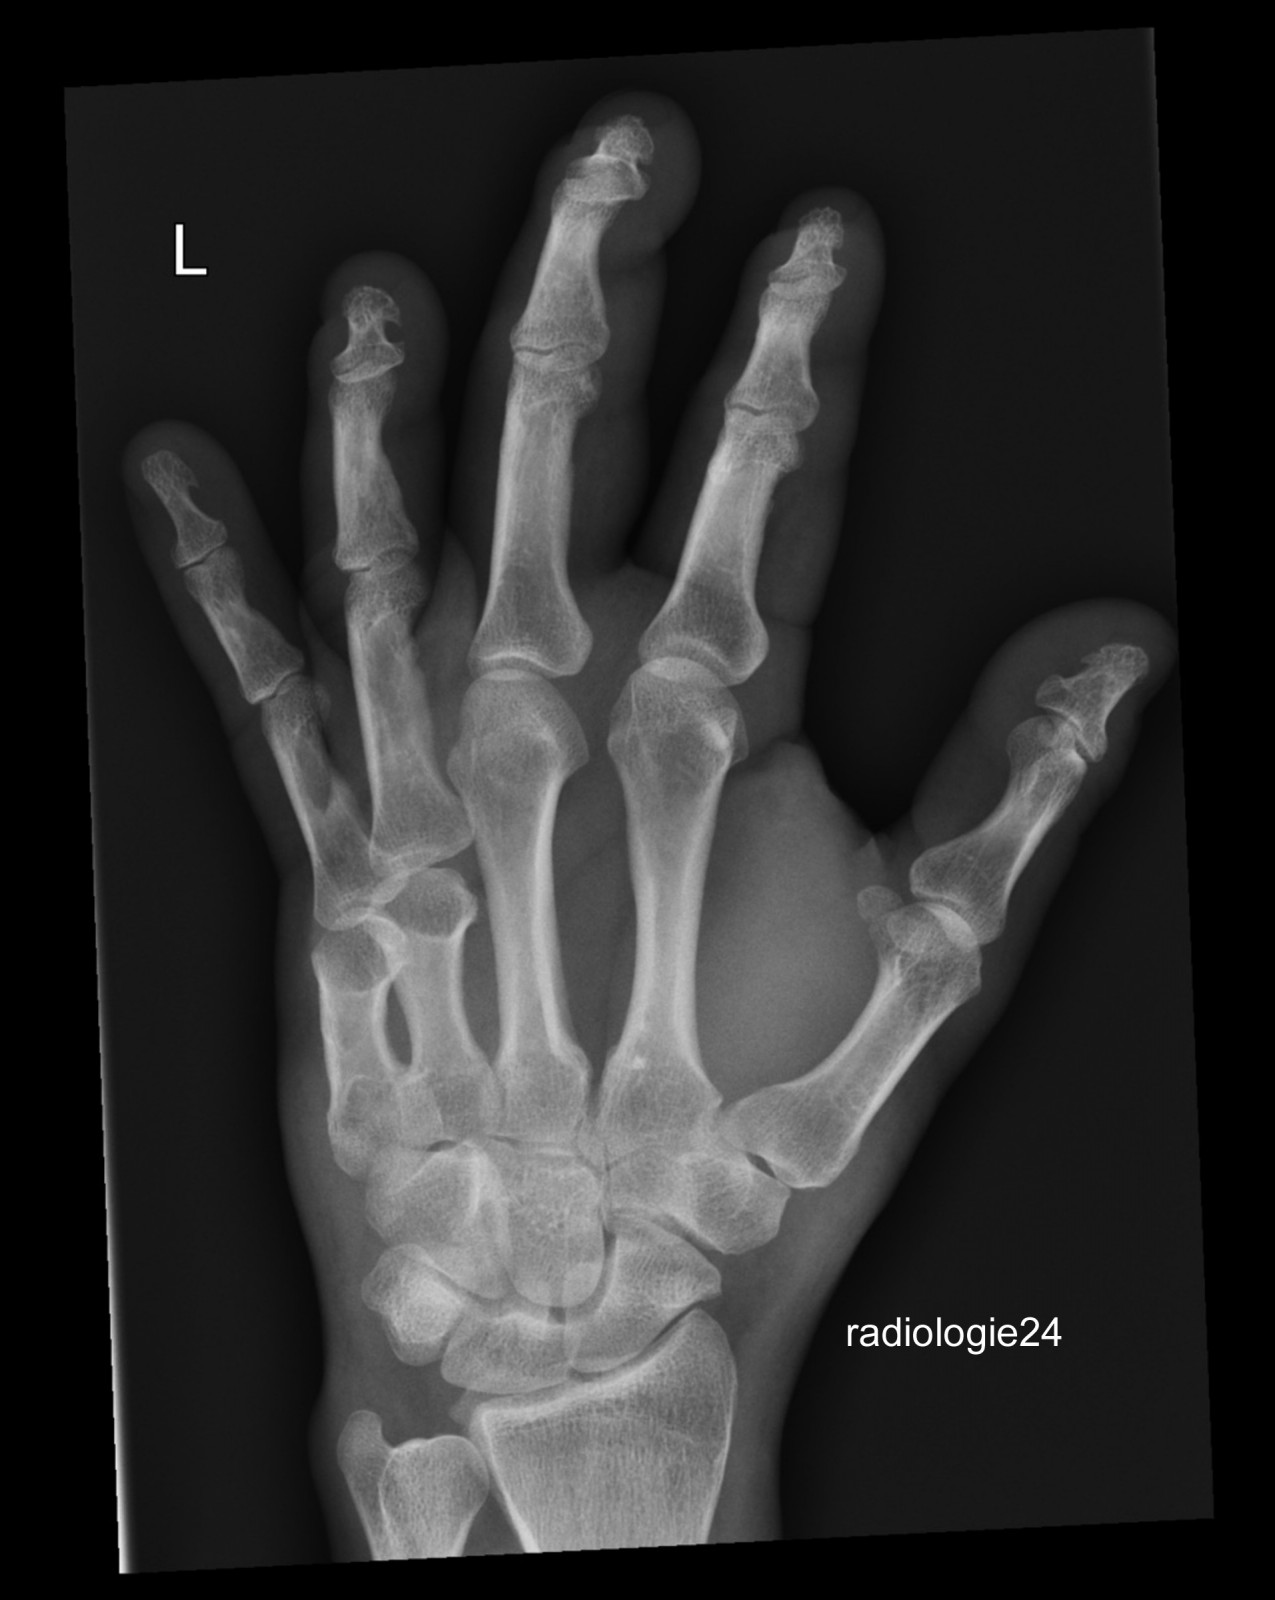

Röntgenfall des Monats Juni 2018 mit Auflösung

45 jähriger Patient Z.n. Sturz. Schmerzen Metacarpalia II/III. Fraktur? Ihre Diagnose?

Bild vergrössern

Link zur Auflösung mit ausführlichem Befund:

https://www.radiologie24.ch/radiologie-mediathek/roentgenfall_des_monats